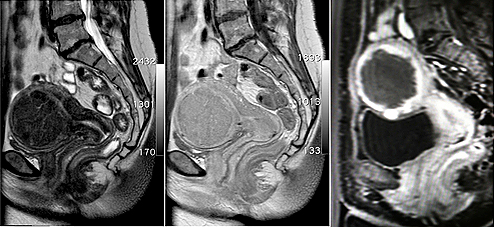

MR-Bilder die ein großes Gebärmuttermyom anzeigen MR-Bilder die ein großes Gebärmuttermyom anzeigen

MR-Bilder vor (linkes und mittleres Bild) zeigt ein großes Gebärmuttermyom. Unmittelbar nach der MR-gesteuerten HIFU-Behandlung (rechtes Bild) ist das Myom zentral nicht mehr durchblutet (dunkel dargestellt)